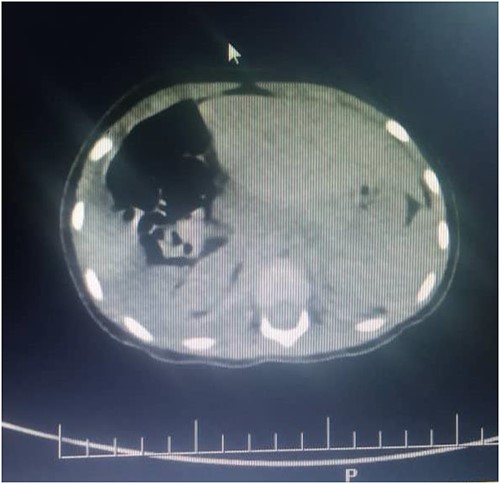

Figures 2 and 3 axial views of thoraco-abdominal CT image taken before laparotomy revealing a ruptured diaphragm of a 1-year-old post trauma patient with reduced right lung volume of expansion.